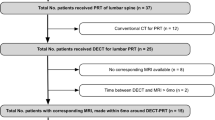

Of the 80 patients who underwent DECT, 67 could be included in the analysis. Mean (SD) age was 70.7 (9.8) years. The median interval between DECT and MRI was 2 days; the mean was 4.4 (9.0) days. Both examinations were tolerated well by all patients. A flowchart of patient inclusion is shown in Fig. 1.

Patient flowchart. A total of 80 patients were imaged using dual-energy computed tomography (DECT), and 13 were excluded because of lacking or incomplete magnetic resonance imaging (MRI) data or failure in DECT postprocessing. The remaining 67 patients were included in the analysis, providing a total of 192 vertebrae with loss of height identified. A total of 294 adjacent disks were defined as target disks and included in the analysis. *One patient was excluded because of incorrect slice orientation of the short tau inversion recovery (STIR) sequence (coronal instead of sagittal). **Three DECT datasets were not accepted by the postprocessing software. ***Lacked agreement between at least two readers

Target disks and endplate involvement

A total of 295 disks were included in the analysis, 190 in the lumbar region and 105 in the thoracic region. Scoring positive in MRI was 194 disks, but in DECT, it was 192 disks (p = 0.59). At least two of the three readers assigned a score of 1 (high STIR signal) to 56 disks, of 2 (high T1 signal) to 40 disks, and of 3 (herniation) to 65 disks. Readers did not agree on the scores for 33 disks (see Fig. 1).